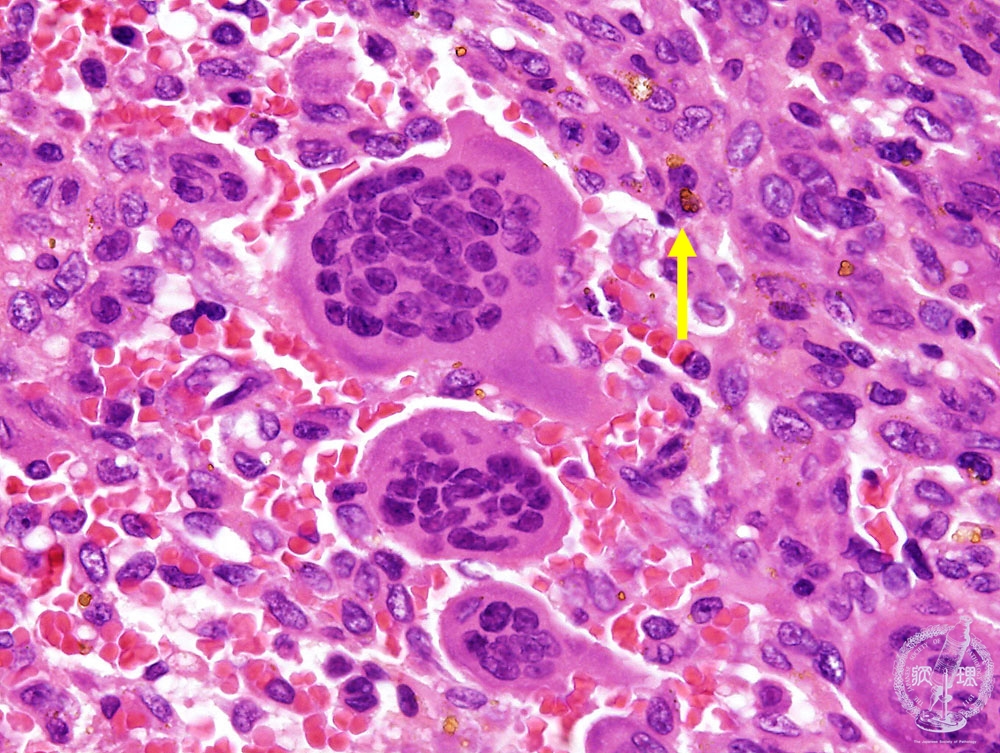

- (9)Giant cell tumor of the bone

Microscopic view (HE; high power view): The number of the multiple nuclei is up to dozens. Hemosiderin deposition is also seen.